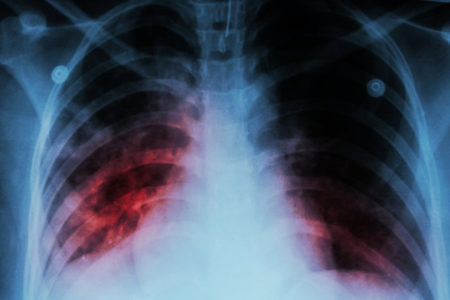

دکتر مهشید ناصحی در گفت‌وگو با ایسنا، با اشاره به شعار امسال روز جهانی سل مبنی بر “مشارکت همه جانبه جامعه، مسیر مطمئن برای دستیابی به حذف سل”، گفت: سل یک بیماری عفونی واگیر است که در اثر میکروبی ایجاد می‌شود که می‌تواند به هر قسمتی از بدن انسان مانند استخوان‌ها، مفاصل، مغز، کلیه، پوست و …حمله و آن‌ها را گرفتار کند، اما به دلیل نیاز و علاقه زیاد این میکروب به اکسیژن، در ۸۰ درصد موارد ریه‌ها را هدف حمله خود قرار می‌دهد.

سل ریوی؛ شایع‌ترین نوع بیماری

وی افزود: با توجه به علاقه زیاد میکروب سل به ریه‌ها، شایع‌ترین نوع بیماری، سل ریوی است که افراد مبتلا معمولا علائمی نظیر سرفه مداوم (به مدت۲ هفته یا بیشتر) دارند که این سرفه‌ها می‌تواند با خلط همراه باشد یا نباشد، تب، کاهش وزن، تعریق شبانه، بی‌اشتهایی، خستگی زودرس و ضعف عمومی و گاهی در مواردی که بیماری دیر تشخیص داده می‌شود درد قفسه سینه، تنگی نفس و خلط خونی دارند.